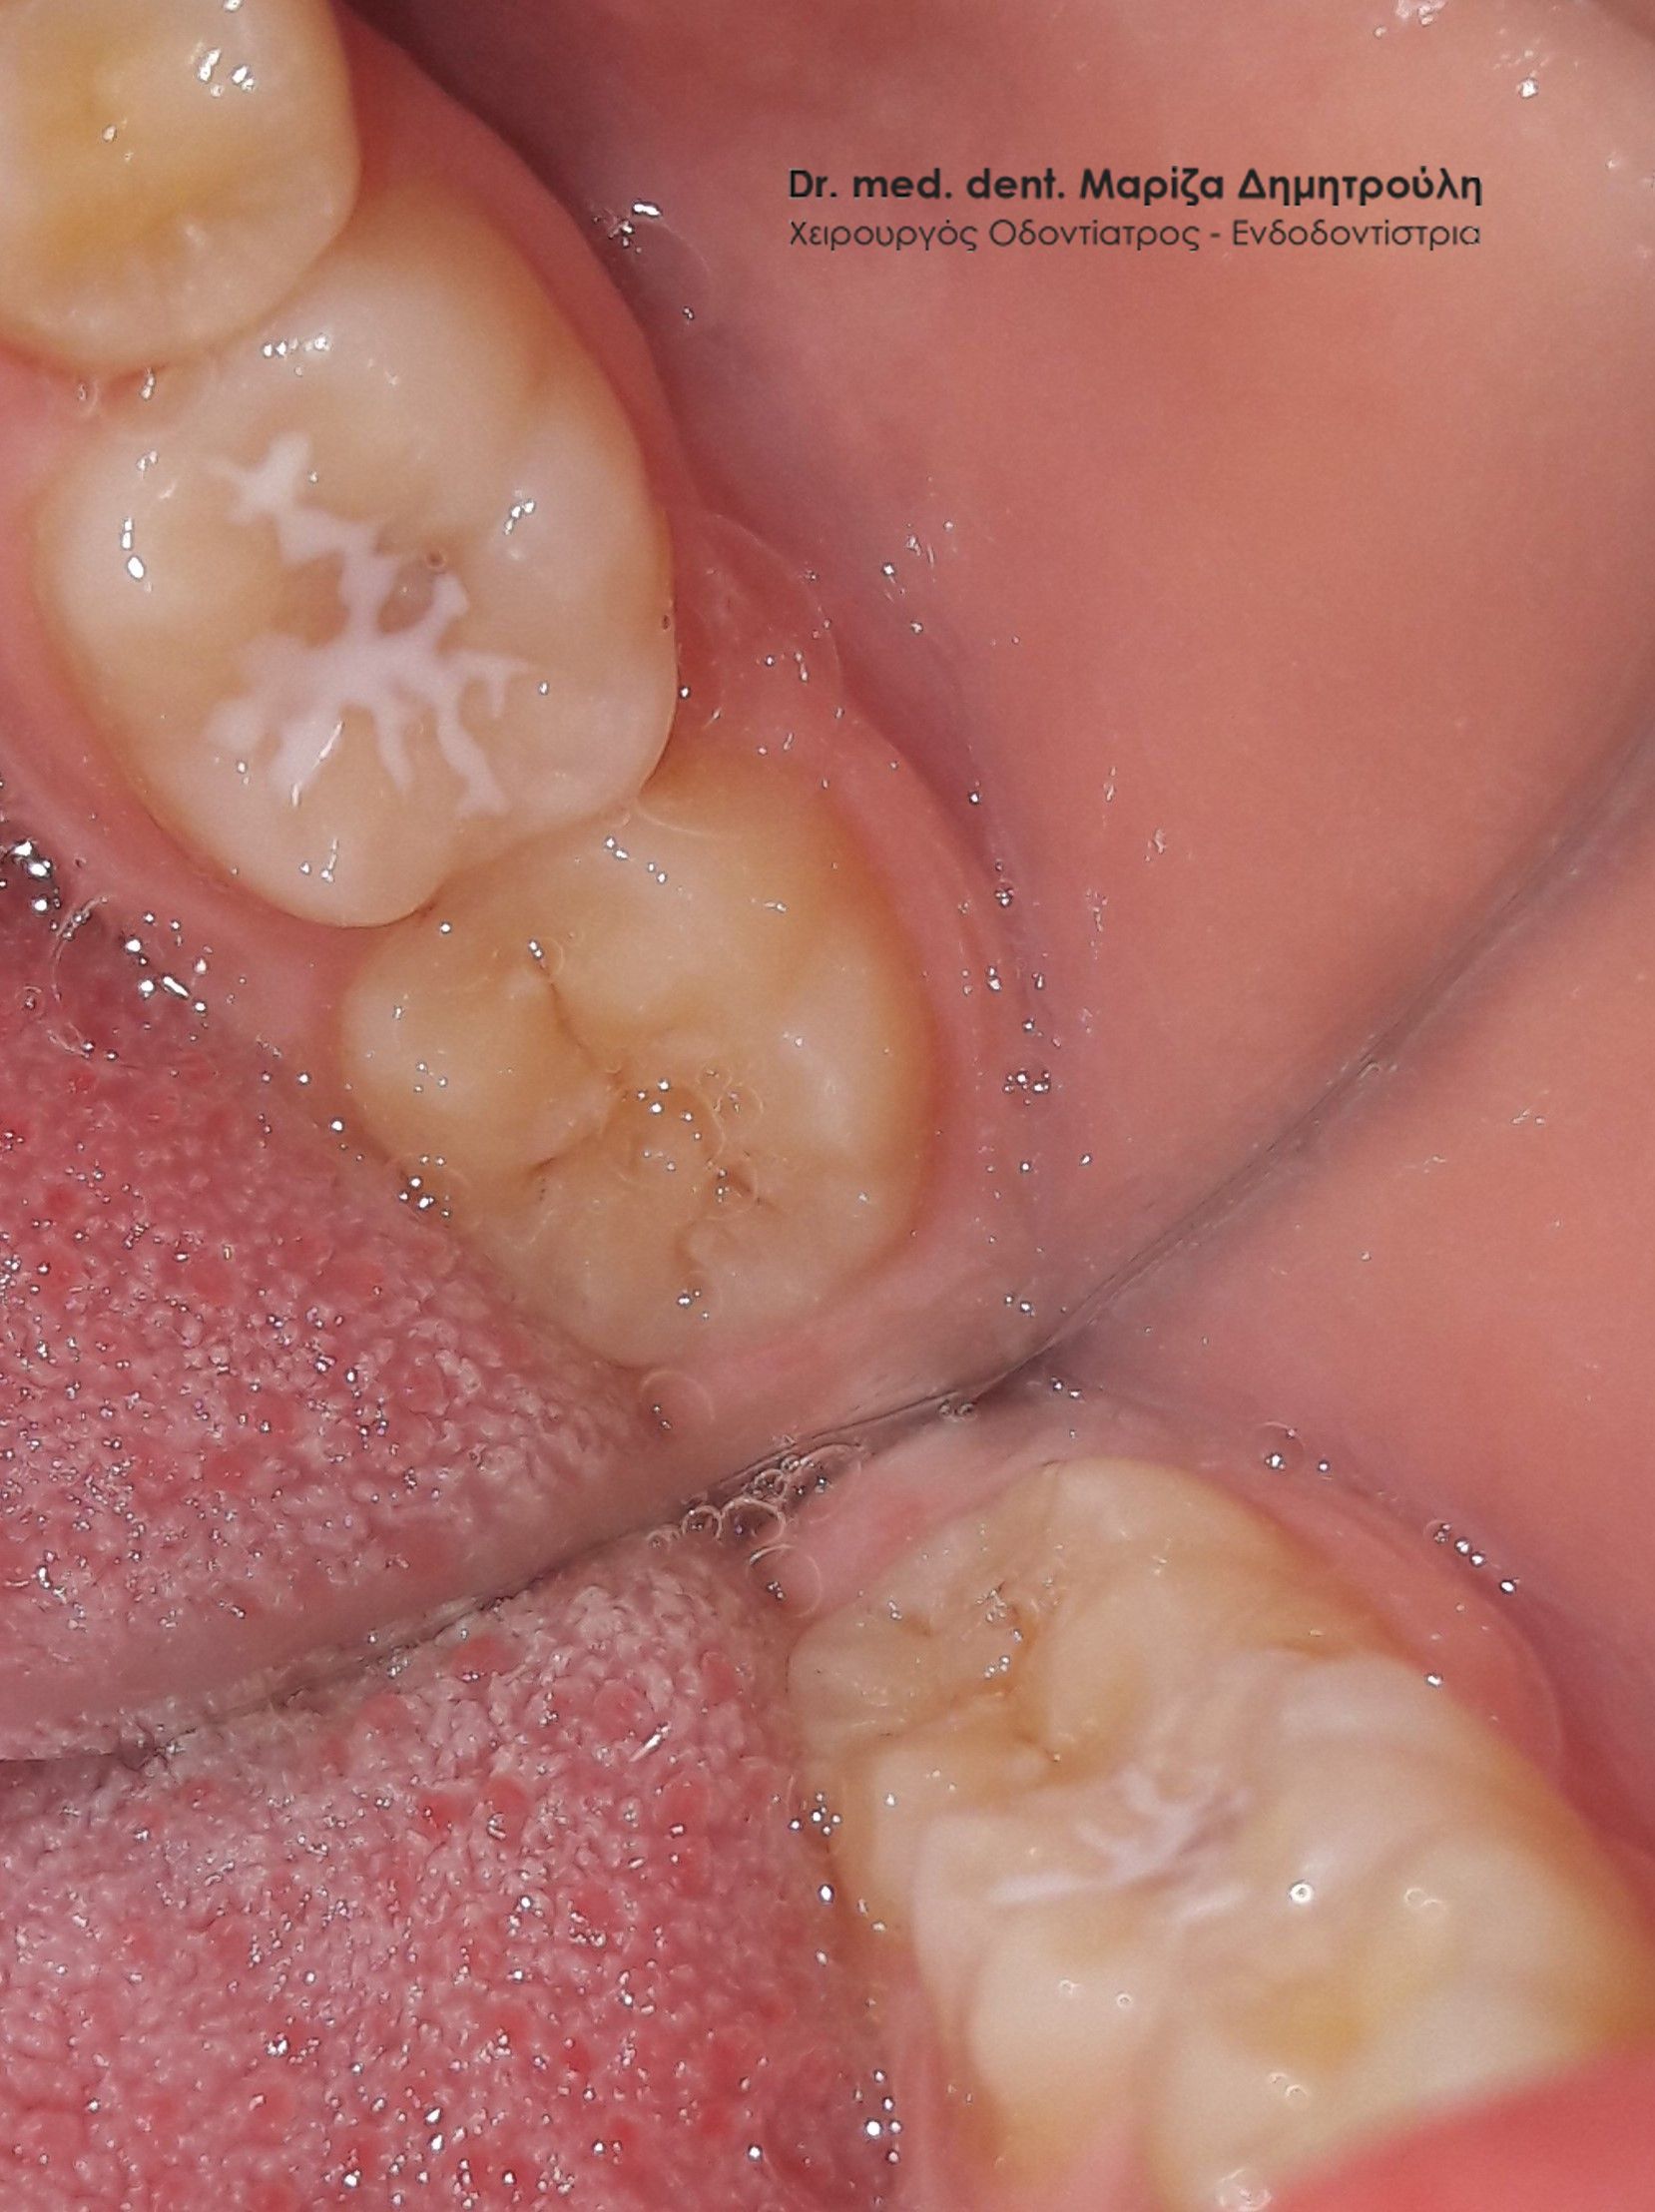

Περιστατικό – Sealant / προληπτική κάλυψη οπών και σχισμών

Στο αγόρι αυτό τοποθετήθηκε προληπτική κάλυψη στη μασητική επιφάνεια του μόνιμου κάτω πρώτου γομφίου, ώστε το δόντι να είναι προστατευμένο από την τερηδόνα. Η κάλυψη της μασητικής επιφάνειας ενός δοντιού με sealant μειώνει την κατακράτηση υπολειμμάτων τροφών στις σχισμές και τις αύλακες του δοντιού αυτού με αποτέλεσμα να συγκεντρώνονται και λιγότερα μικρόβια στο δόντι. Παράλληλα το παιδί μπορεί να βουρτσίζει πιο αποτελεσματικά και εύκολα τα πίσω δόντια καθώς μειώνονται οι πτυχές του δοντιού, όπου παγιδεύονται συνήθως τροφές.

Ο χρόνος ζωής ενός sealant κυμαίνεται από 2 – 5 χρόνια.

ΠΡΙΝ